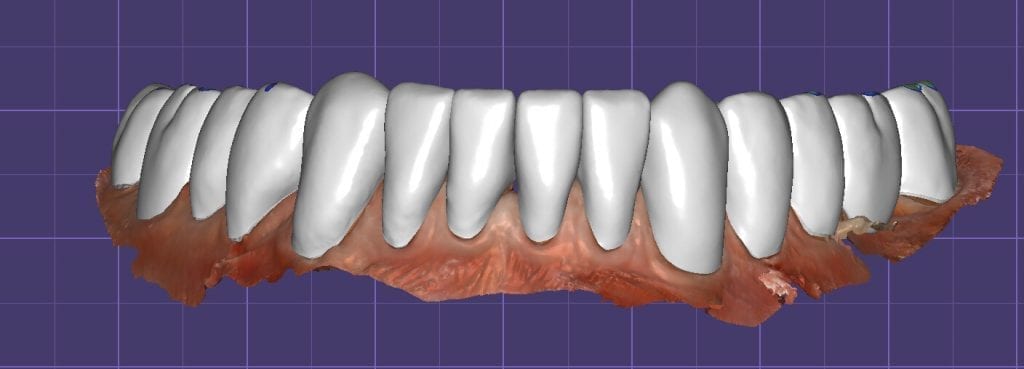

Over the course of a few appointments, the vertical dimension was reduced and the temporaries were adjusted to the patient’s desires. The new upper and lower arch were captured with the Medit i500 and the jaws were related to each other.

This was then imported into exocad where the prepped arches from a few weeks prior were force matched to the new bite

After the upper jaw was related to the temps, the same was done with the lower arch. Great care was taken to make sure the arches were properly related to each other throughout the process